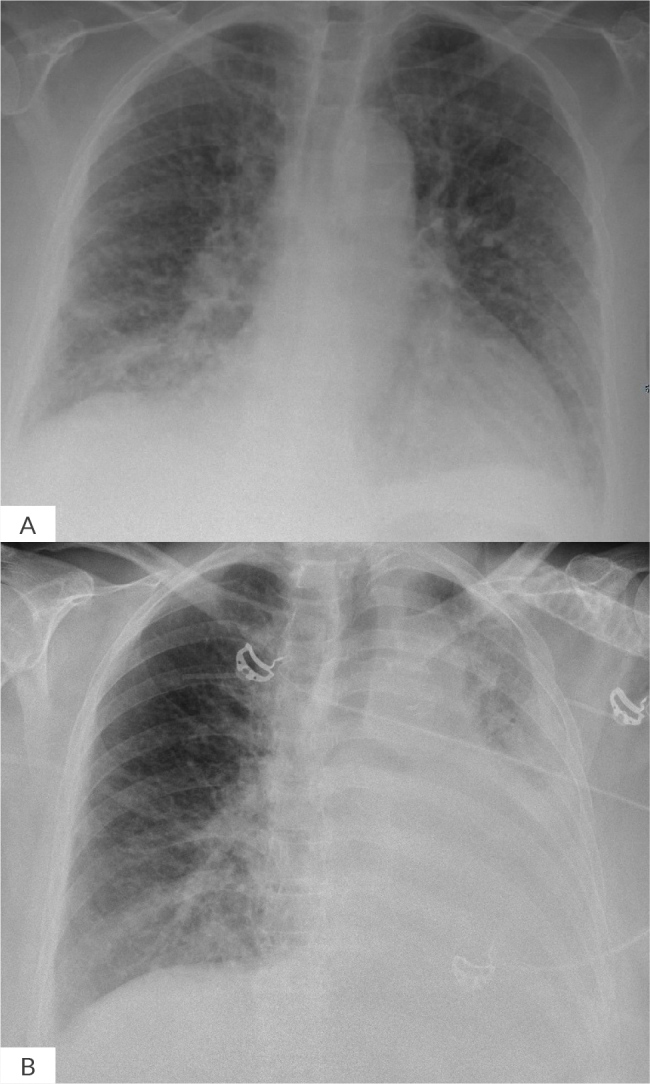

A 70-year-old woman, hospitalised for asymptomatic hyponatraemia secondary to syndrome of inappropriate antidiuretic hormone secretion (SIADH), required emergency intubation due to severe acute respiratory failure and haemodynamic instability following broncho-aspiration of a salt tablet. We hypothesise that a pathophysiological mechanism resembling saltwater drowning may have contributed to the clinical presentation.

Learning points: Salt tablet broncho-aspiration could be associated with severe hypoxaemia and haemodynamic instability.The pathophysiology of salt tablet broncho-aspiration may mimic drowning in saltwater.